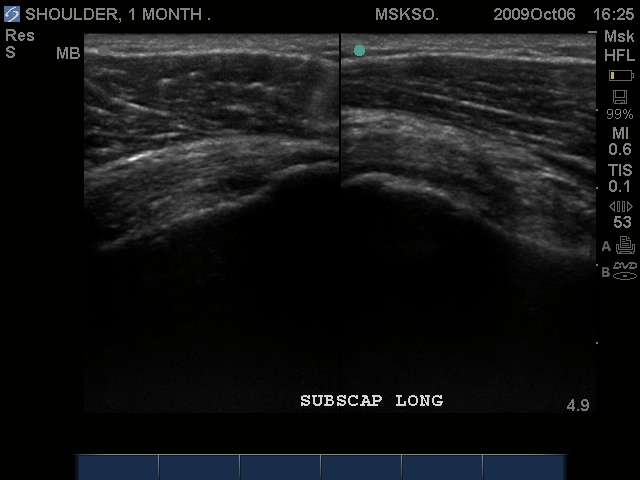

Long axis (left) and Transverse (right) images of Subscapularis Tear